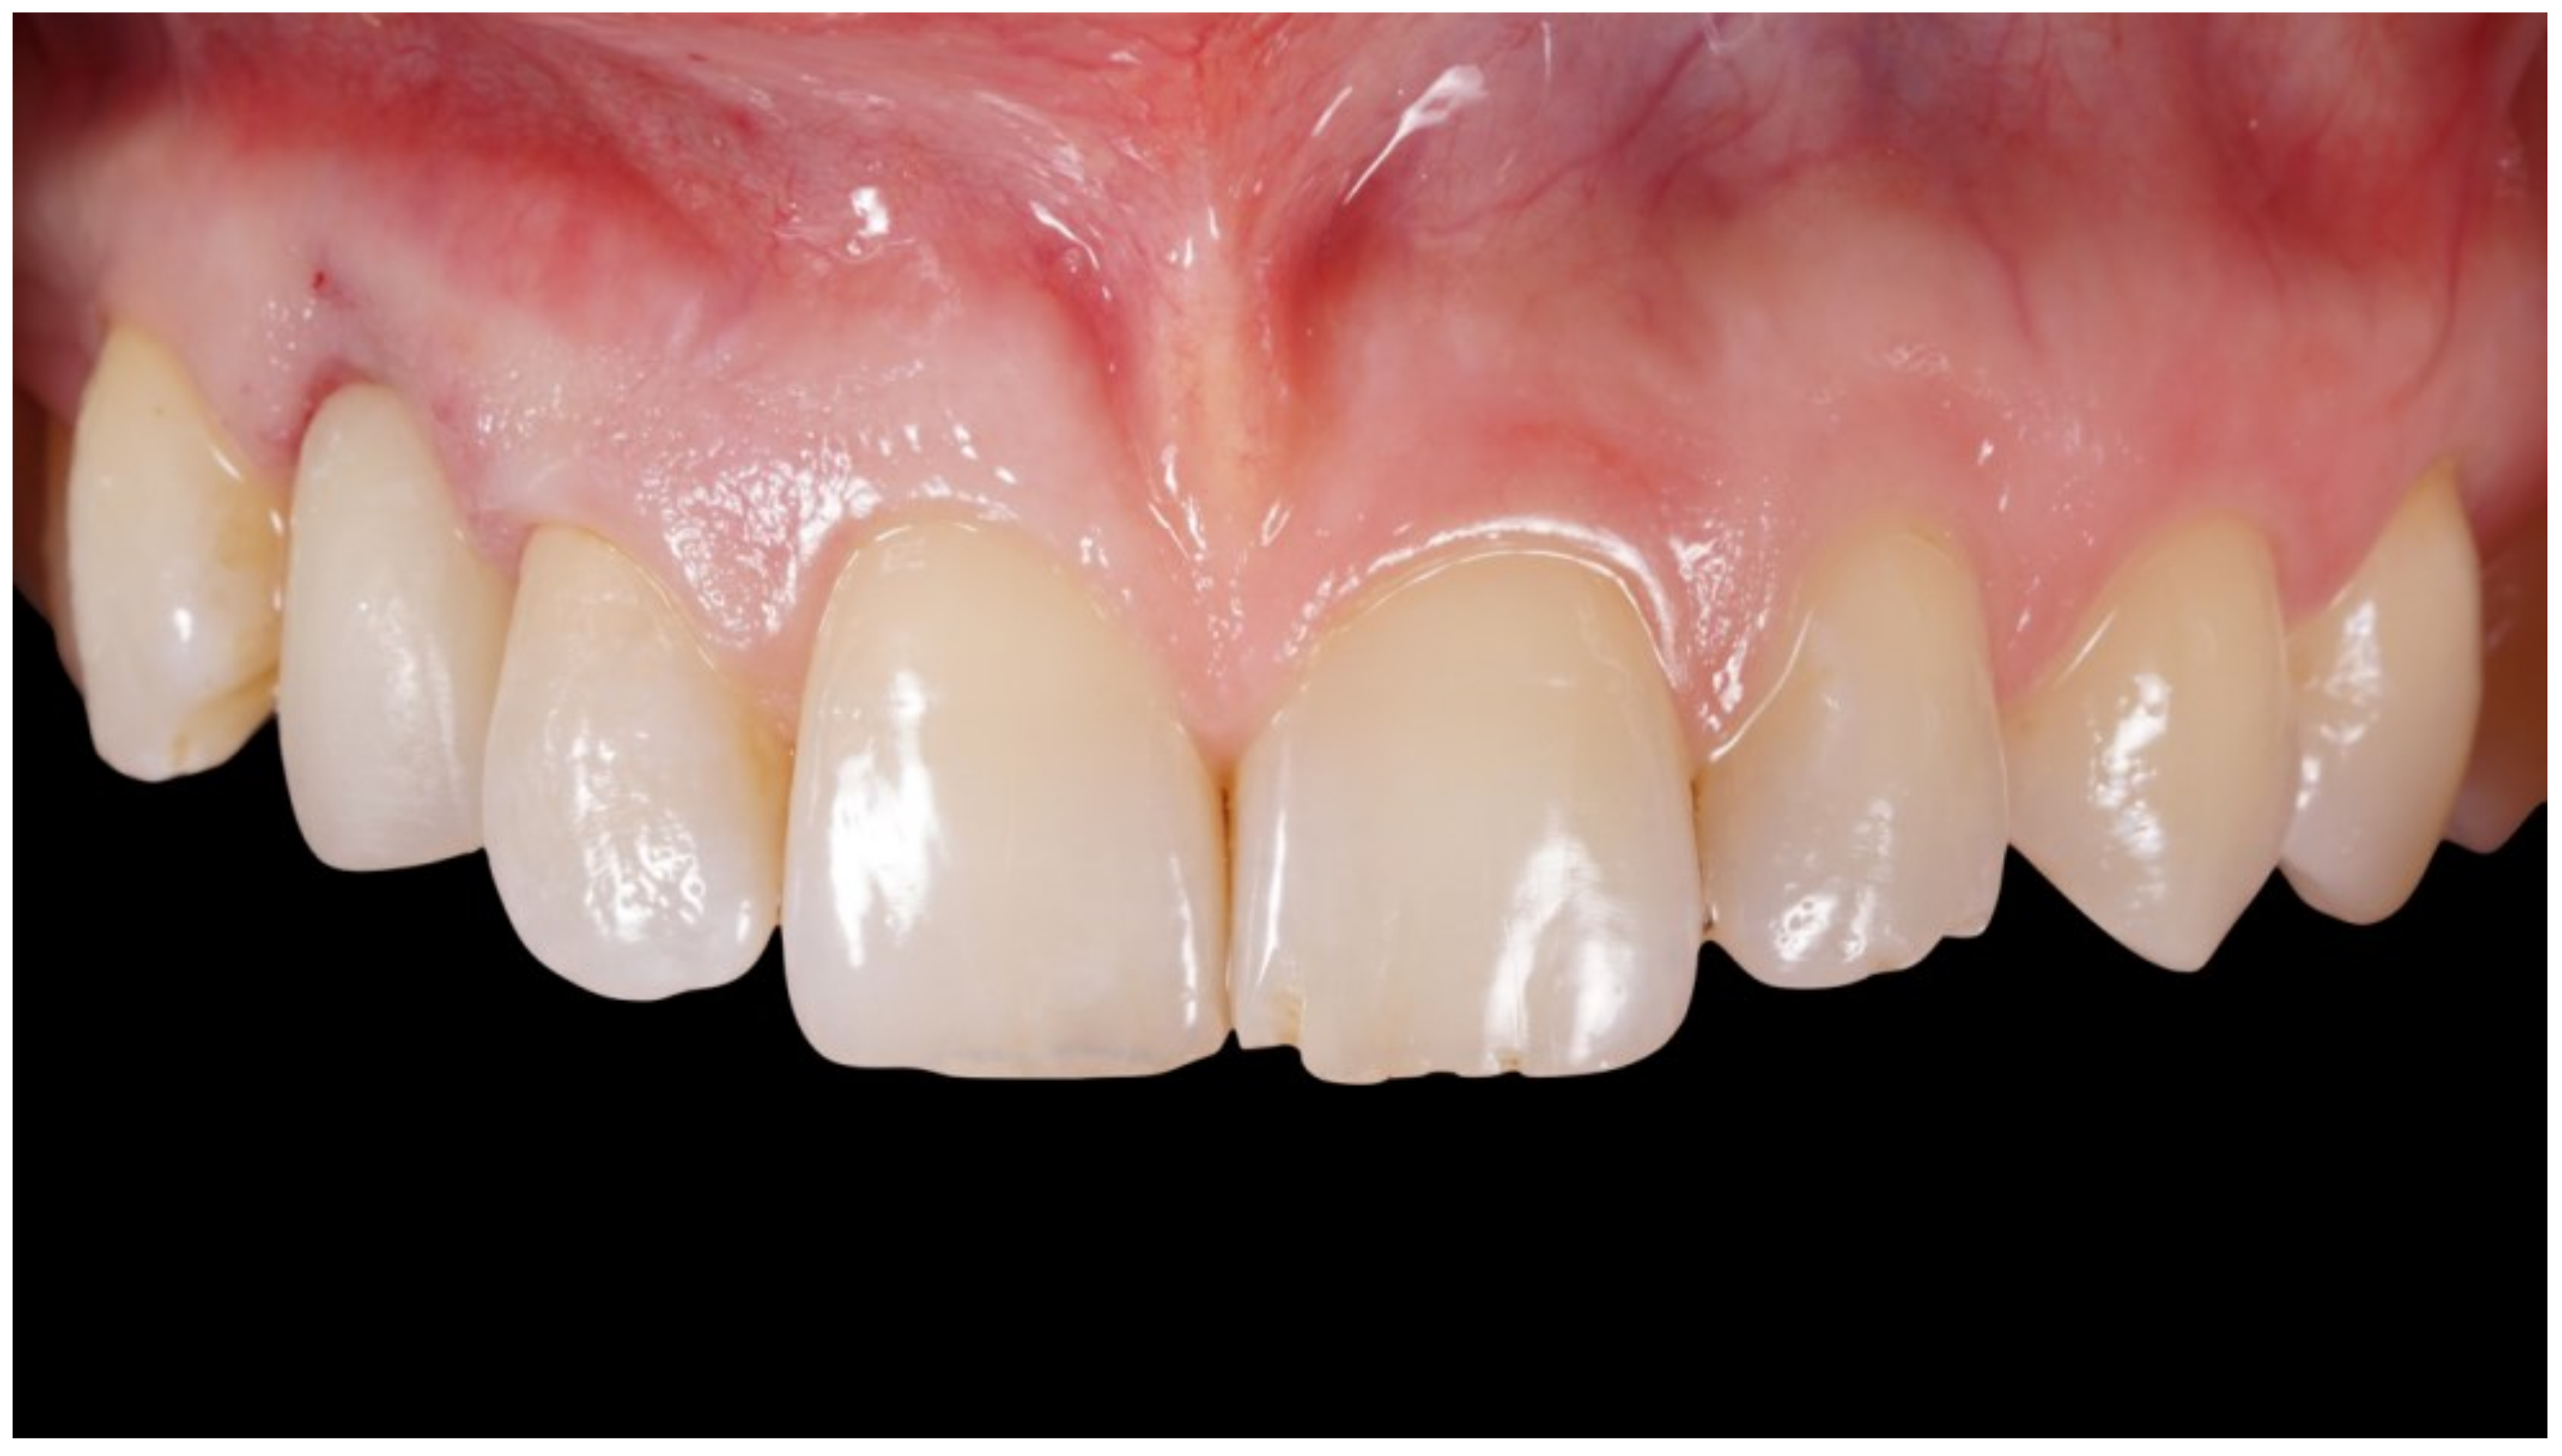

The final prostheses were screw-retained lithium disilicate fused on zirconia custom abutments. The definitive crown was screwed to 35 Ncm and the screw channel was filled with composite resin (Figure 8, Figure 9 and Figure 10).

Figure 8.

Delivery of final crown.

Figure 9.

Definitive crown after 1 year of follow-up, frontal view.